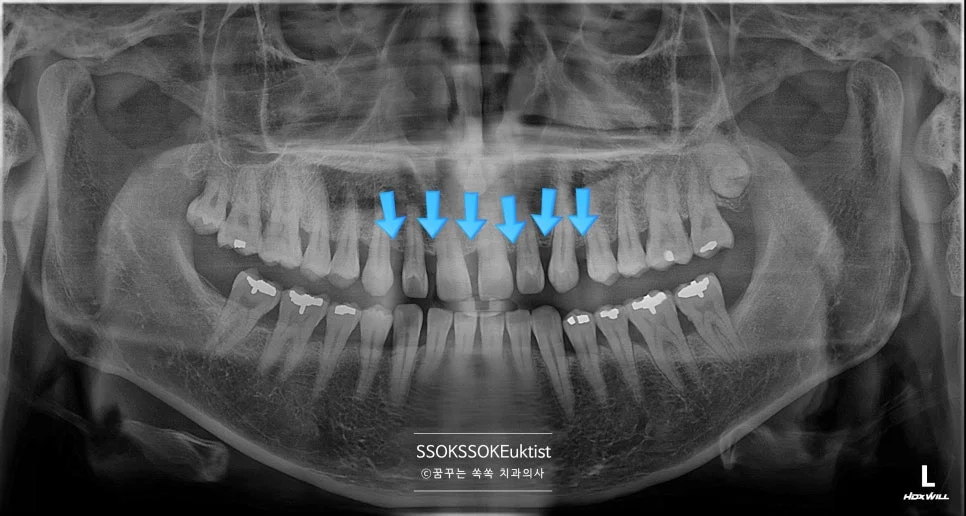

신경치료 통증 없이 받으려면? 치수염 진단부터 크라운까지 전 과정

신경치료 케이스1 초진 파노라마 엑스레이

좋은 진료를 정직하게 | 선한 영향력으로 더 나은 가치를 신경치료 통증 없이 받으려면? 치수염 진단부터 크라운까지 전 과정 꿈꾸는 쏙쏙 치과의사 박상억입니다 오늘은 치과 치료의 화룡정점이라고 할 수 있는 치아의 신경치료에 대해 설명드릴까 합니다. 신경 치료는 그 이름부터 무시무시한데 실제 통증과 감각을 느끼는 신경 그 자체를 다루는 치료다 보니 엄청난 통증이 있는 상태에서 아주 편안한 … 더 읽기